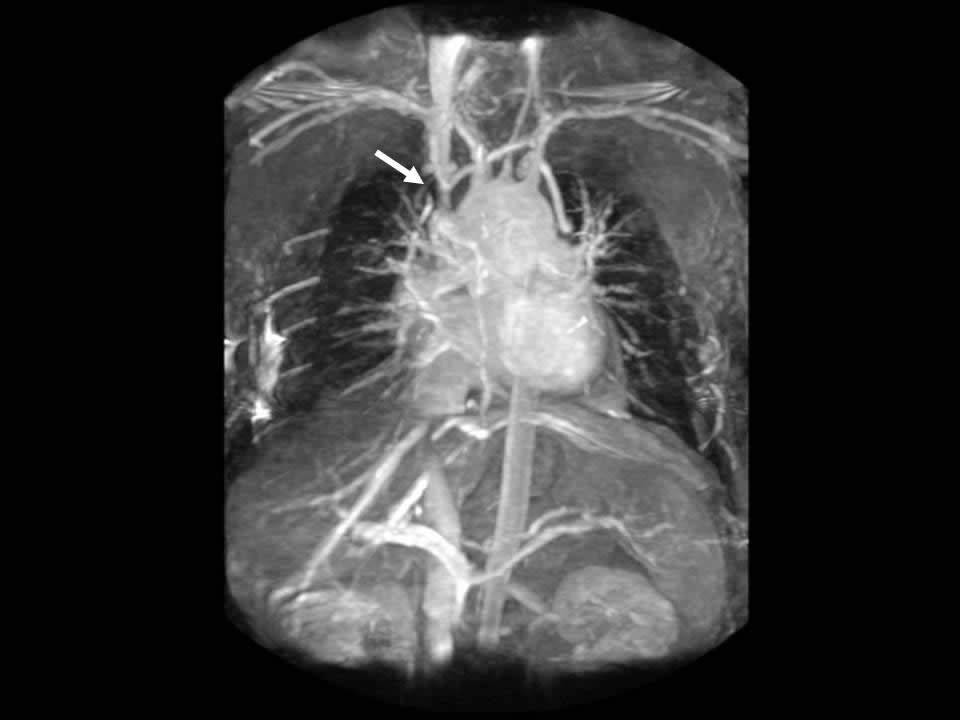

| Figure 1 |

On physical exam the patient had an obviously swollen head without cyanosis, but with multiple collaterals over her chest and upper neck. An MRA was obtained which demonstrated complete obstruction of the superior vena cava below the brachiocephalic junction (Figure 1). There were also significant collaterals through the intercostals and internal mammary veins, but no evidence of intrathoracic mass, adenopathy, or evidence of vein thrombosis.